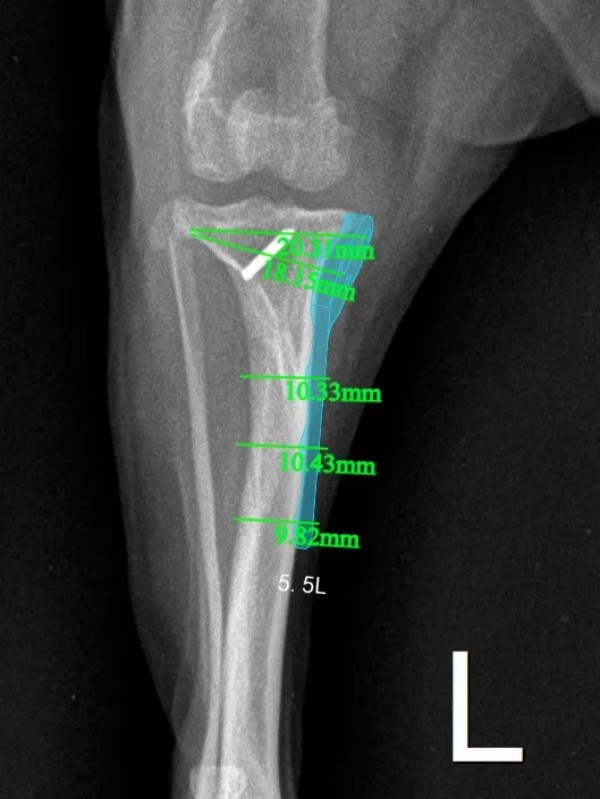

术前X光片

DR:膝关节加压,胫骨前倾。